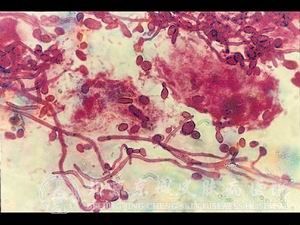

长期服用广谱抗生素容易染上念珠菌病是什么?北京京城皮肤医院介绍,很多患者会自行买药治疗疾病,特别是念珠菌病,它是一种真菌性皮肤病,如果使用的药物不恰当,会导致真菌大量繁殖,不仅不能治疗念珠菌病,还会引起念珠菌病症状加重。现在我来听听介绍:为什么长期服用广谱抗生素容易染上念珠菌病?

很多患者都不知道,长期服用广谱抗生素容易染上念珠菌病是什么?北京京城皮肤医院为您简单介绍。

北京京城皮肤医院指出,了解完长期服用广谱抗生素容易染上念珠菌病是什么,有助于我们更快地找到适合自己的念珠菌病治疗方法,了解完广谱抗生素会引起念珠菌的抗药性,破坏体内的菌群平衡。这样我们可以 地接受念珠菌病的治疗。